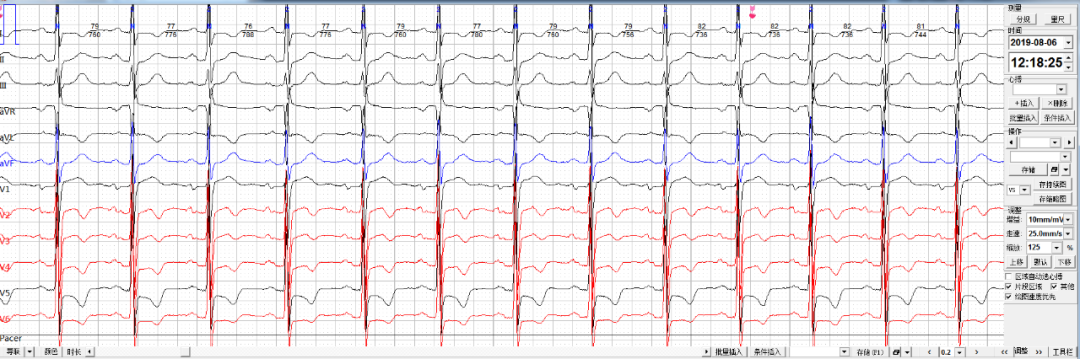

每日一图丨NO.664 同一患者出现如下六幅心电图改变,如何判断?乐普医疗AI关注2021-01-20 14:14 心电图解析(NO.663)今日读图(NO.664)患者姜某,男性,66岁。佩戴心安宝24小时动态心电监护仪,监测到如下片段如何分析诊断?诊断完毕后要记得将答案写在留言区哦 浏览 51点赞 评论 收藏 分享 手机扫一扫分享分享 举报 评论图片表情视频评价全部评论推荐 每日一图丨NO.658 患者的心电图出现如下改变,请诊断?乐普医疗AI0每日一图丨NO.682 患者出现如下心电改变,如何诊断?乐普医疗AI0每日一图丨NO.646 患者出现如下心电改变,如何诊断?乐普医疗AI0每日一图丨NO.654 如下三幅心电图出自同一位患者,该如何诊断?乐普医疗AI0每日一图丨NO.680 窦性心律患者出现如下心电改变,如何诊断?乐普医疗AI0每日一图丨NO.643 26岁女性患者心电图改变如何诊断?乐普医疗AI0每日一图丨NO.637 这位患者心电图如何诊断?乐普医疗AI0每日一图丨NO.635 两幅图同一患者出现如下心电变化该如何诊断?乐普医疗AI0每日一图丨NO.675 请判断患者出现何种心电异常改变?乐普医疗AI0每日一图丨NO.678 71岁男性患者出现如下心电改变,请分析。乐普医疗AI0点赞 评论 收藏 分享 手机扫一扫分享分享 举报